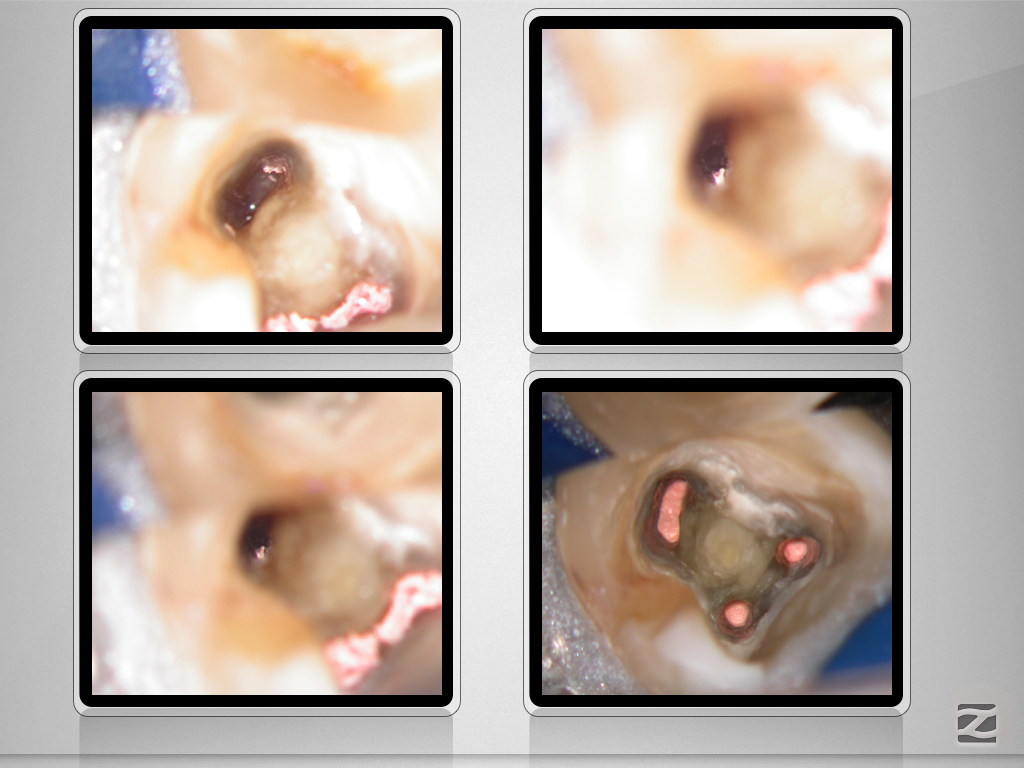

37D.002

X-Bein mit Kommunikation